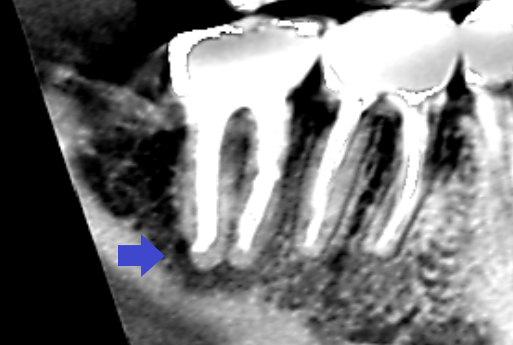

精密根管治療6カ月後の経過観察時の矢状断のCT画像です。矢印の先にみられた膿の影が消失し歯槽骨が再生してきています。